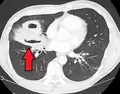

| Computed tomography (CT) scan of chest showing bilateral pneumonia with abscesses, effusions, and caverns. 37-year-old male. | |

Pulmonary abscess on CT scan -